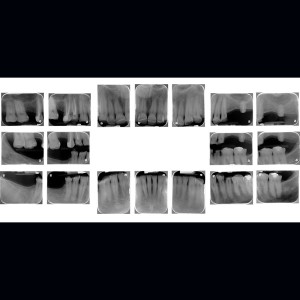

SERVICIOS 2D

SIALOGRAFIA